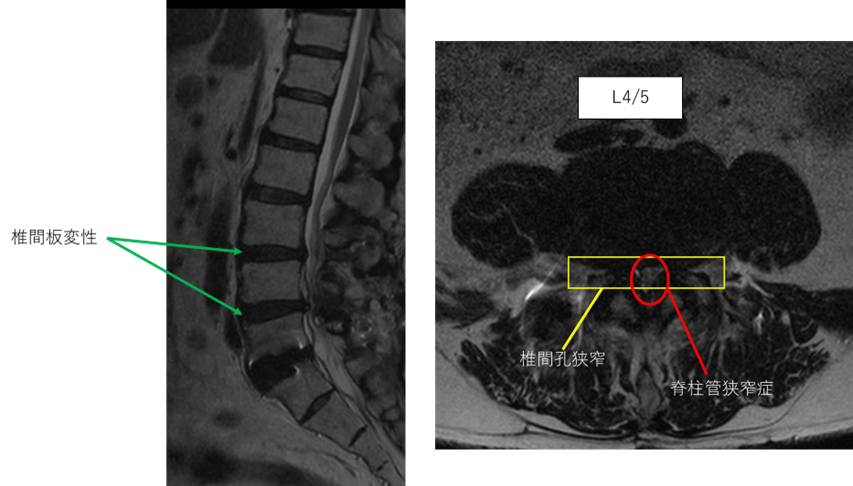

画像及び所見について

L1/2: 異常なし

L2/3: 異常なし

L3/4: 椎間板変性症、両椎間孔狭窄

L4/5: 椎間板変性症、両椎間孔狭窄、脊柱管狭窄症

L5/S: 固定術後

以上の事が画像上認められます。

L3/4,4/5 に

椎間板変性症、両椎間孔狭窄、脊柱管狭窄症を認め、主症状の原因の可能性が高い。